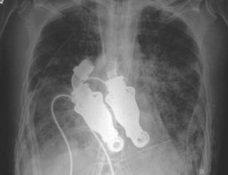

The heart is arguably one of the most vital organs and back in 2011, doctors were able to develop a machine that allowed Craig Lewis to live without a pulse.

After decades of trial and error, two doctors at the Texas Heart Institute developed a device that used whirling rotors to replace the heart’s pumping function.

Cohn and Frazier were able to remove the man’s heart and replace it with their revolutionary device.

Linda said: “I listened and it was a hum, which is amazing. He didn’t have a pulse.”

The doctors said that the pump should last longer than other artificial hearts and would even cause fewer problems.